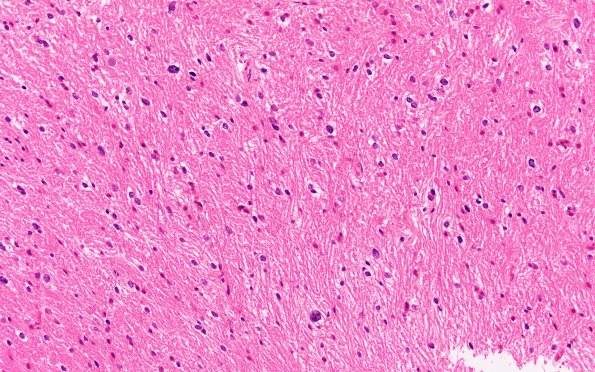

Washington University Experience | NEOPLASMS (GLIAL) | High-Grade Astrocytoma with Piloid features (HGAP) | 3B2 HGAP (Case 3) H&E 20X

The tumor appears minimally cellular in this area characterized by infiltrating scattered pleomorphic nuclei. The tumor cells have minimal discernible cytoplasm and oval to irregular atypical enlarged nuclei with dense chromatin (H&E)